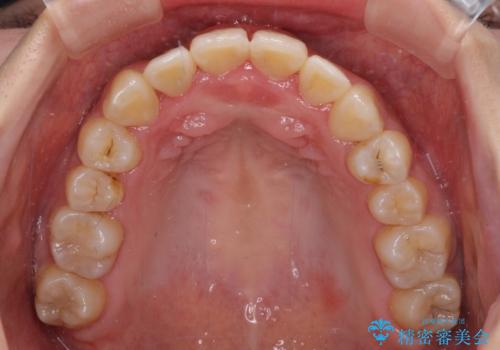

前後に重なった前歯 ワイヤー装置と急速拡大装置を併用したインビザライン矯正

- 前歯の著しい叢生とクロスバイトを気にして来院された患者様です。

叢生が強いため、一見すると抜歯矯正と判断したくなりますが、下顎臼歯が舌側に倒れていることから、上顎骨を側方拡大し、非抜歯矯正の可能性を検討することとしました。

急速拡大装置による上顎骨の側方拡大が思った以上にうまくいき、非抜歯での矯正が可能となりました。

内側に倒れていた下顎の臼歯は起き上がり、清掃性も大幅に改善されました。